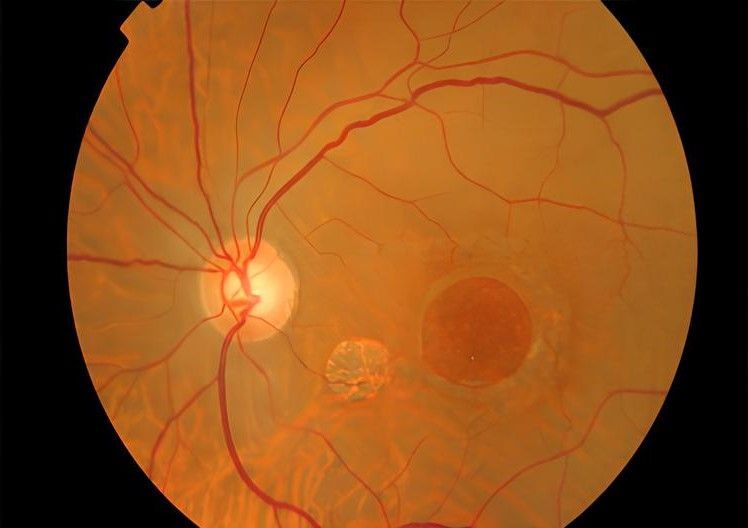

Le Trou Maculaire (TM) est une affection oculaire qui se caractérise par la présence d'un petit trou ou d'une déchirure dans la macula, la partie centrale de la rétine responsable de la vision fine et détaillée. Ce trouble peut être causé par plusieurs facteurs, tels que le vieillissement, la dégénérescence maculaire, les traumatismes oculaires ou d'autres maladies rétiniennes.

Les patients atteints de Trou Maculaire peuvent présenter des symptômes tels qu'une vision déformée ou déformée, une vision floue ou une diminution de l'acuité visuelle. Le diagnostic du TM est réalisé par un examen complet de la rétine, comprenant des tests de vision, une dilatation de la pupille et des techniques d'imagerie avancées telles que l'OCT (Tomographie en Cohérence Optique). L'OCT permet de visualiser le trou maculaire et d'évaluer son impact sur la structure de la macula.